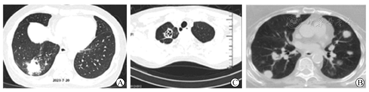

高分辨率计算机断层扫描(CT)是肺部IFD的首选影像学检查方法。IFD典型的影像学表现包括结节、肿块、节段性或亚节段性实变、肺不张、磨玻璃影、树芽型、空洞或胸腔积液;然而,这些影像学表现可在其他肺部感染或炎症过程中遇到。在特定的临床背景下,晕征、反晕征、低密度征和空气新月征等表现有助于区别IFD和非真菌性肺炎[23]。结节和团块影是SOT受者最具特征性的IFD影像学表现,但实变等非特异性表现也可能是唯一的表现[24]。单发的结节团块影需要和原发性肺癌进行鉴别。一般来说,原发性肺癌在CT影像通常呈现为单发的肺实质内的肿块或结节,呈现不规则形状,边界模糊或分叶状,同时还可能伴随肺门淋巴结增大、胸膜增厚或胸腔积液。而IFD典型的影像学表现为结节团块影周围伴有晕征、或可能存在包括结节、团块影的节段性或亚节段性实变、肺不张、磨玻璃影、树芽征、空洞伴空洞内新月征,或胸腔积液;侵袭性肺曲霉病(in-vasive pulmonary aspergillosis,IPA)是所有的SOT受者肺部IFD的最常见类型。IPA包括血管侵袭性改变和气道侵袭性改变,疾病早期影像学常呈现非特征性的气道病变,如支气管周围实变影、支气管扩张征、小叶中心型微小结节影、毛玻璃样改变等;随疾病进展,曲霉侵犯肺部血管,影像学检查则表现为晕轮征、肺实变、空气新月征等特征性改变,其中,晕轮征具有较高的临床诊断价值[24,25]。此外,与血液恶性肿瘤患者不同,SOT受者IPA的影像学(图2)常为非特征性改变[23,26,27]。